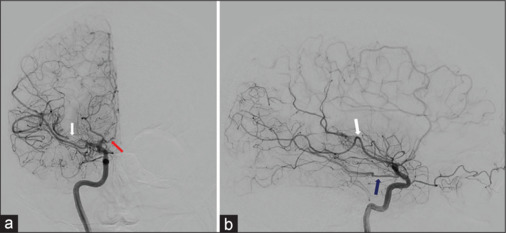

烟雾病(MMD)是一种以颅内动脉进行性闭塞为特征的脑血管疾病,常导致脑卒中和脑出血。虽然烟雾病通常影响颅内血管系统,但我们报告了一个不寻常的双侧椎体狭窄闭塞病例,导致37岁烟雾病患者椎基底动脉功能不全,并通过血管成形术和椎动脉支架置入术治疗。回顾文献显示椎动脉近端受累是烟雾病的罕见表现。该报告有助于了解烟雾病的临床谱,并强调需要警惕和意识到受影响个体颅内外血管并发症的可能性。

Moyamoya disease (MMD) is a cerebrovascular disorder characterized by progressive occlusion of intracranial arteries, often leading to stroke and intracerebral hemorrhage. While MMD classically affects the intracranial vasculature, we present an unusual case of bilateral vertebral steno-occlusion, resulting in vertebrobasilar insufficiency in a 37-year-old man with MMD and treated with angioplasty and stenting of the dominant vertebral artery. Review of the literature demonstrates proximal vertebral artery involvement to be a rare manifestation of moyamoya disease. This report contributes to the understanding of the clinical spectrum of MMD and emphasizes the need for vigilance and awareness of the possibility of extracranial vascular complications in affected individuals.